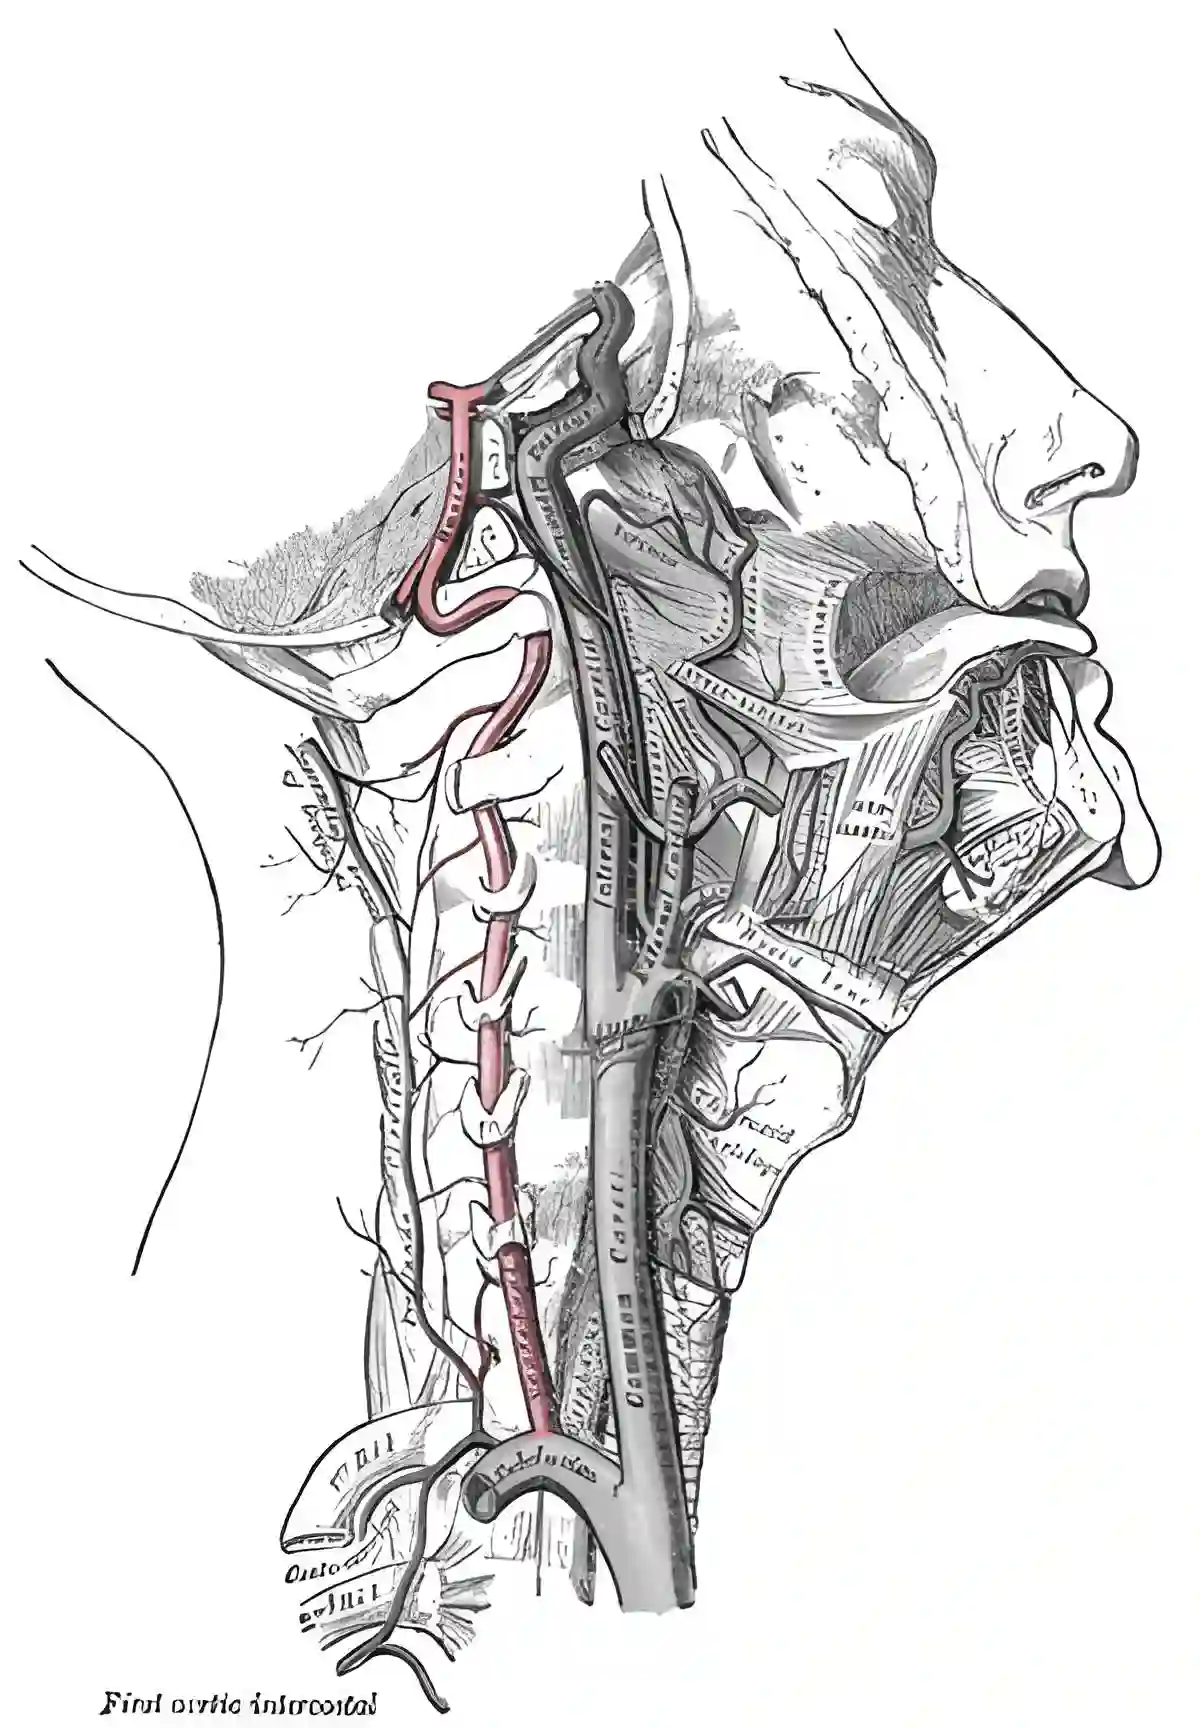

Die Arteria vertebralis ist für die Hauptversorgung des hinteren Stromgebiets des Gehirns verantwortlich.

Die paarig angelegte Arteria verterbralis entspringt aus der Arteria subclavia und vereinigt sich zur Arteria basilaris. Die Arteria vertebralis kann in vier Segmente unterteilt werden[^1]:

Prevertebrales Segment (V1) | Das V1 Segment verläuft vom Arterienabgang bis zum Eintritt in das Foramen transversarium, üblicherweise auf Höhe HWK6 | Keine |

Foraminales Segment (V2) | Das V2 Segment verläuft vertikal in den Foramina transversaria in der Halswirbelsäule entlang. |

Predurales Segment (V3) | Das V3 Segment verläuft vom Austritt der Arteria vertebralis aus dem Foramen transversarium des Axis bis zum Eintritt der Arteria vertebralis in die Dura mater. |

Intradurales Segment (V4) | Das V4 Segment verläuft vom sehr variabel gelegenen Duradurchtritt bis zur Vereinigung zur Arteria basilaris. |